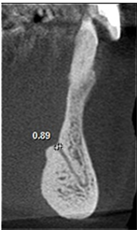

The following measurements were performed: longest width of the genial canal (W) or (D); longest length of the genial canal in relation to the alveolar bone crest (L) or (L1); (D1) or (L2), which was performed between the uppermost portion of the genial plexus and the alveolar bone crest (for dentate patients the reference was the buccal bone crest); shortest distance from the genial plexus to the buccal cortical bone (D2) or (L3), which was performed between the most vestibular portion of the genial plexus and the buccal cortical bone; (D3) or (L4), which was performed between the lowest portion of the genial plexus and the cortical part of the mandible base (Figures 1(B)-(D)).

Figure 1. Tomographic images, diameters and distances of the canal and plexus. (A) Parasagittal tomographic image; (B) Canal diameter; (C) Distance from the genial plexus to the cortical bone; (D) Initial parasagittal tomographic image, central incisor tooth. Source: Own Authorship. Caption: Parasagittal tomographic image measuring the length (A) canal diameter (B) and distances as follows: (L1) of the genial canal; (L2) distance from the genial plexus to the alveolar bone crest, (L3) distance from the genial plexus to the buccal cortical bone and the base of the mandible (L4) (C), initial parasagittal tomographic image (D). Figure 1 (A) Parasagittal section of the CBCT used to perform measurements. (B) Longest width of the genial canal (W). (C) longest length of the genial canal (L). (D) Shortest distance from the genial plexus to the alveolar bone crest (D1); shortest distance from the genial plexus to the buccal cortical bone (D2); shortest distance from the genial canal relative to the base of the mandible (D3).